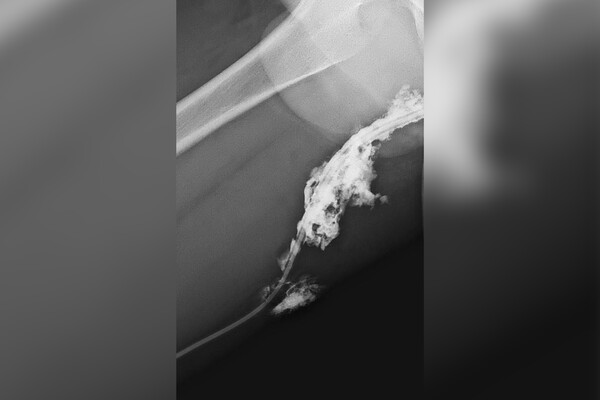

Подросток прыгнул с гаража и приземлился бедром на острый прут металлического забора. В больнице пострадавшему провели рентген с контрастом для выявления инородных тел в мягких тканях.

«Прут вошел достаточно глубоко, вплоть до седалищного нерва. Тем не менее, к счастью, жизненно важные структуры организма не были повреждены», — рассказал врач-травматолог-ортопед больницы Александр Нестеренко.